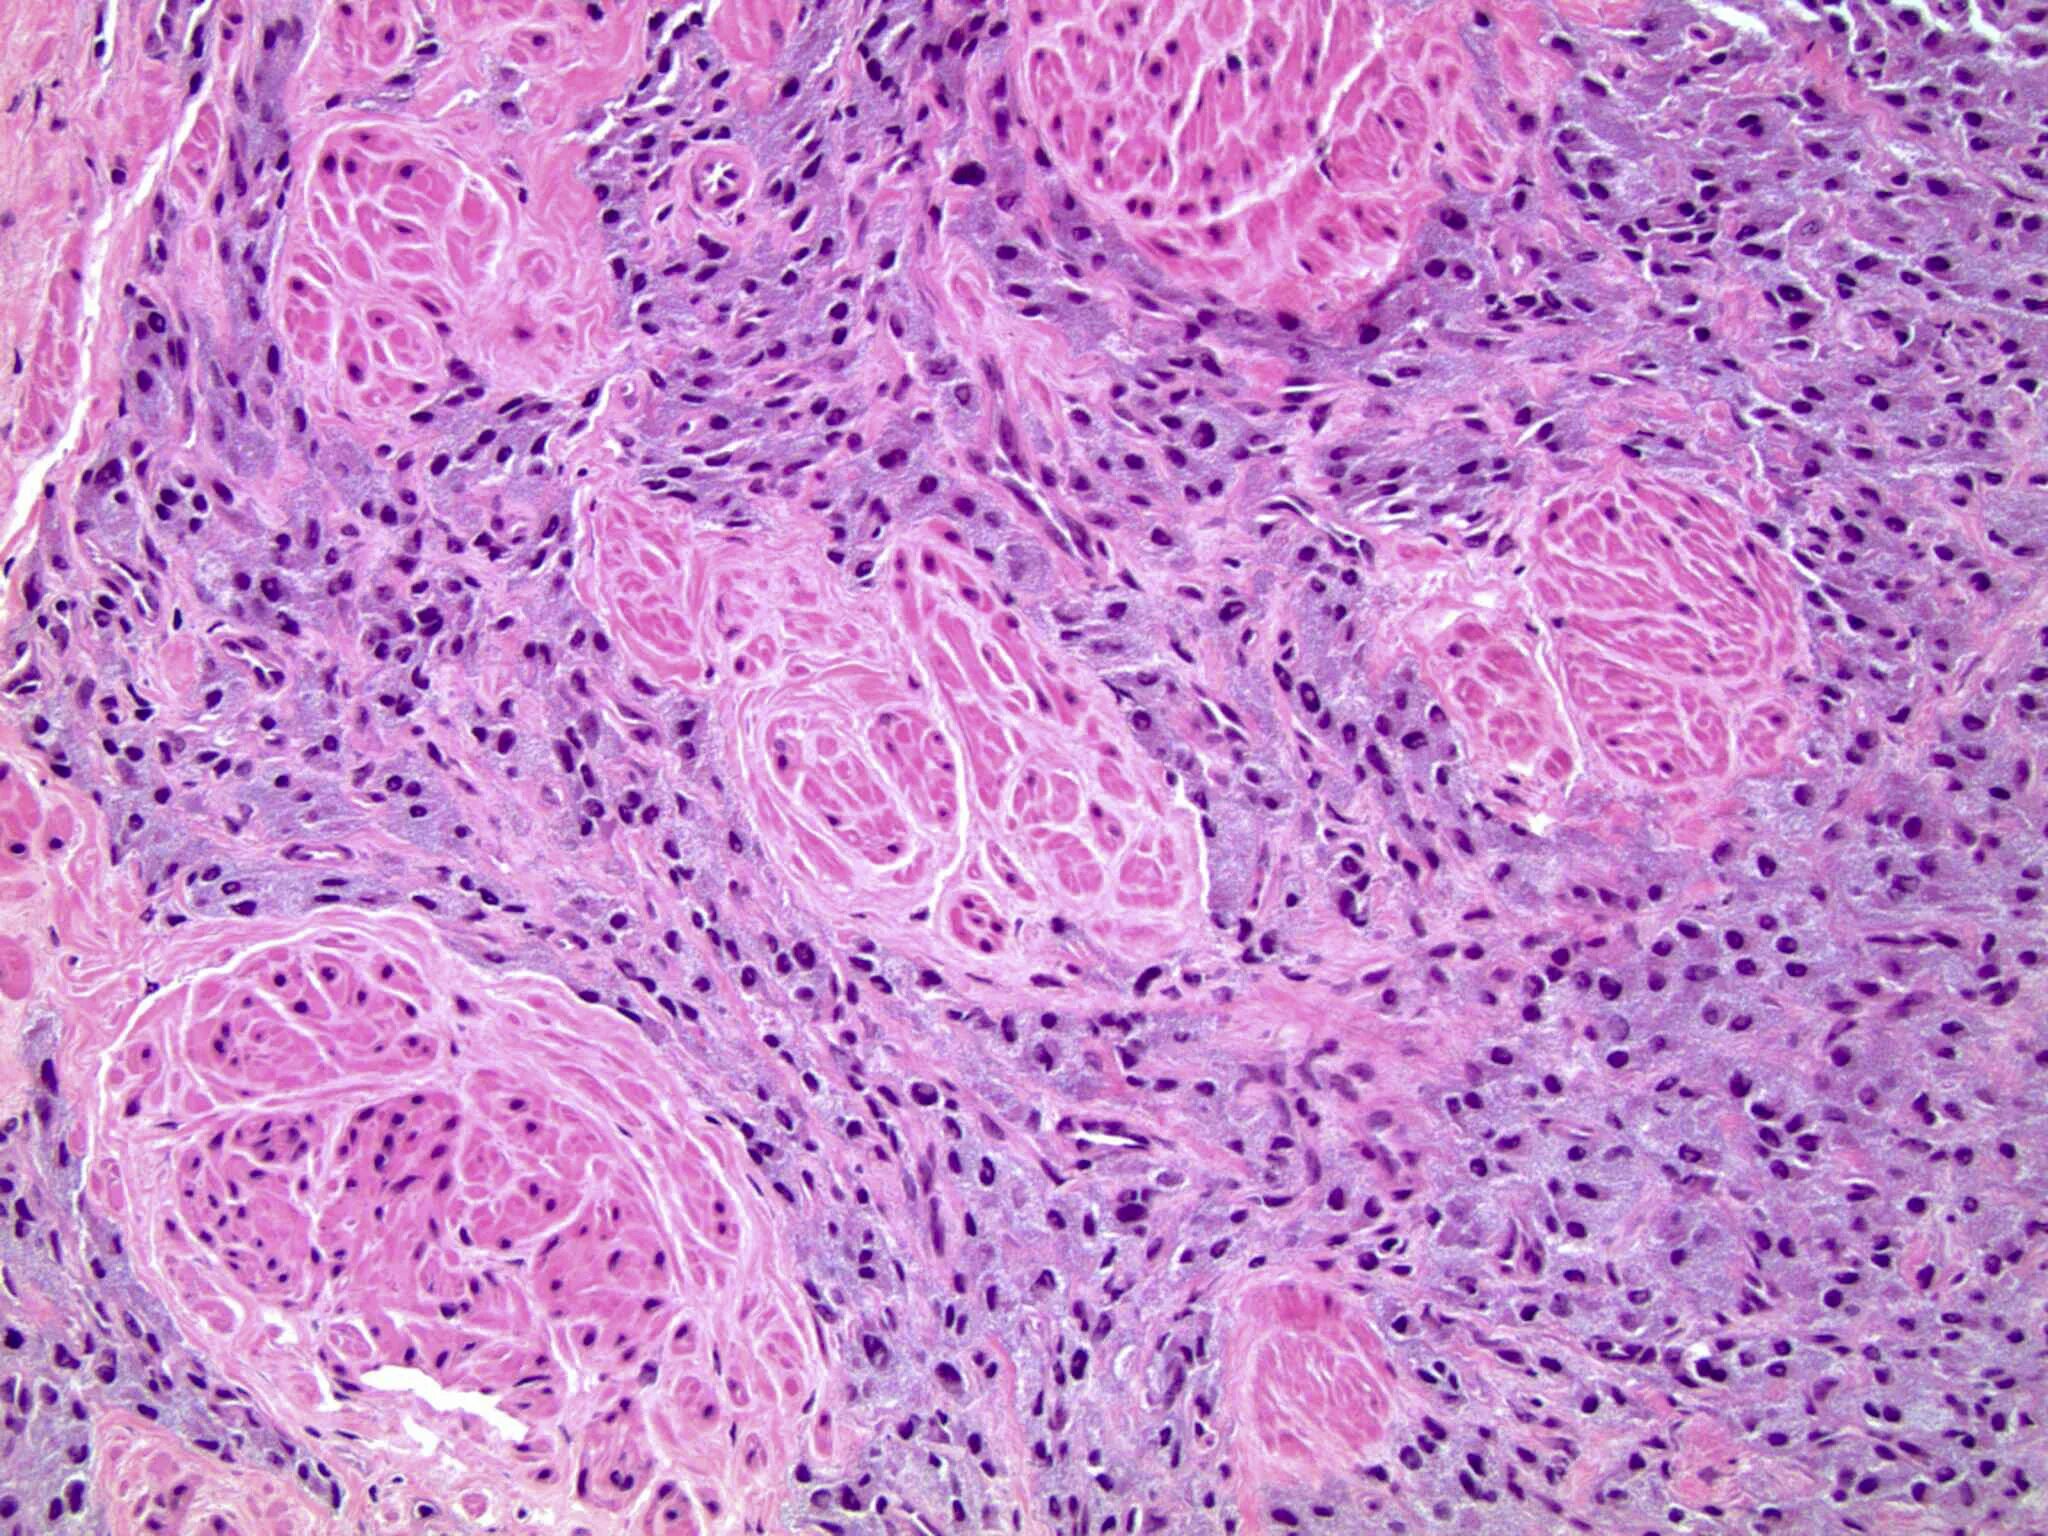

Что показала гистология замершей